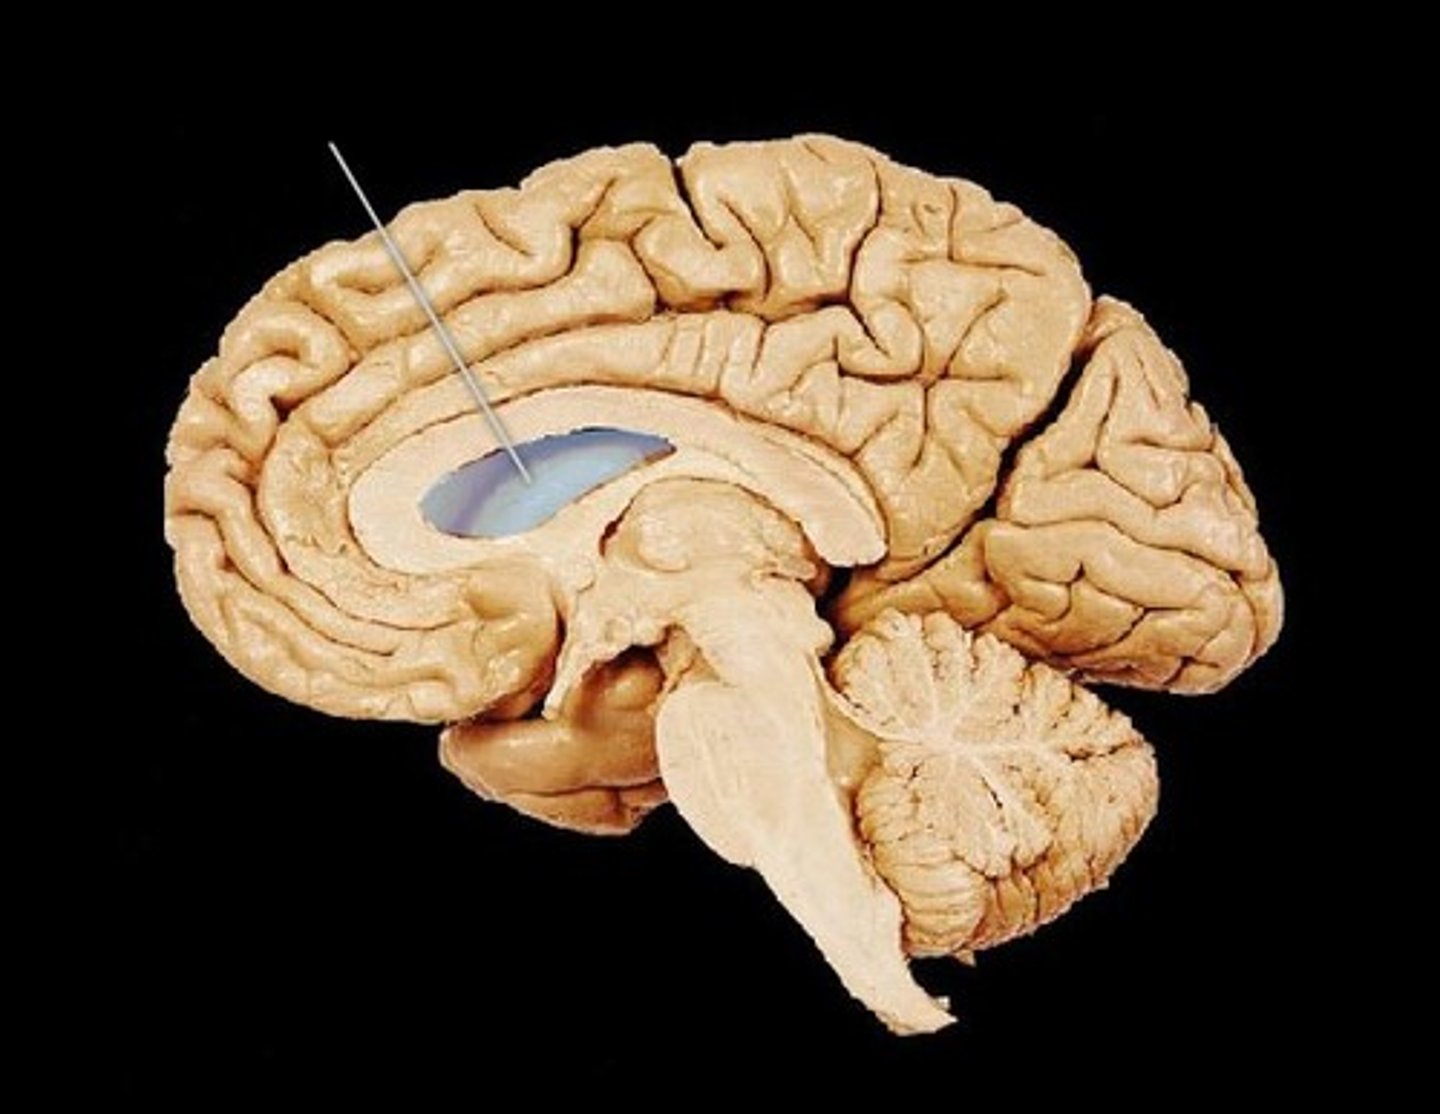

Corpus Callosum

Fibers connecting both halves of the brain, c shaped structure

Fornix

fiber tract linking limbic system regions

Septum Pellucidum

separates lateral ventricles

lateral ventricle

2 lateral ventricles. one in each cerebral hemisphere.

third ventricle

formed from diencephalon. Superior to hypothalamus; lies between right/left halves of thalamus